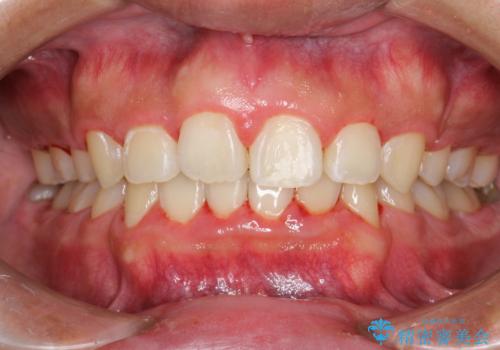

ワイヤー矯正終了時に装置除去と合わせてPMTC

担当医 歯科衛生士